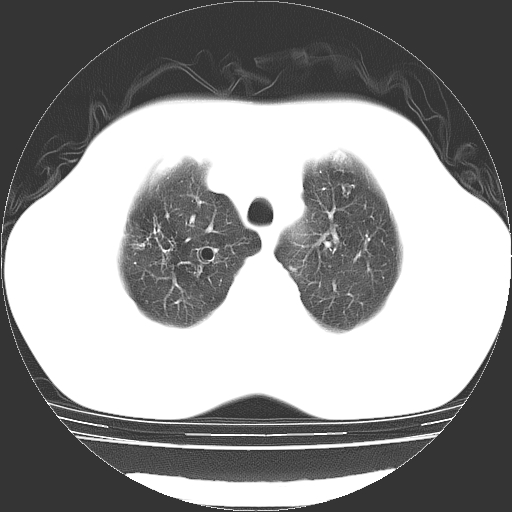

以下是引用zyx168在2006-12-4 15:30:00的发言:[br]经典!支气管肺囊肿并感染。

以下是引用dyqct在2006-12-4 17:11:00的发言:[br]典型的囊状支扩合并感染。

以下是引用liaoqiang在2006-12-4 16:12:00的发言:[br]局部肺叶内可见扩张的支气管壁,考虑为支扩。部份囊样影内有小液平和肺内散布斑片征影、小结节及纤维灶,提示支扩伴感染,且由于局部呈现有树芽征感染以结核可能性大。

以下是引用zhoucan076在2006-12-4 16:48:00的发言:[br]囊状支扩合并感染